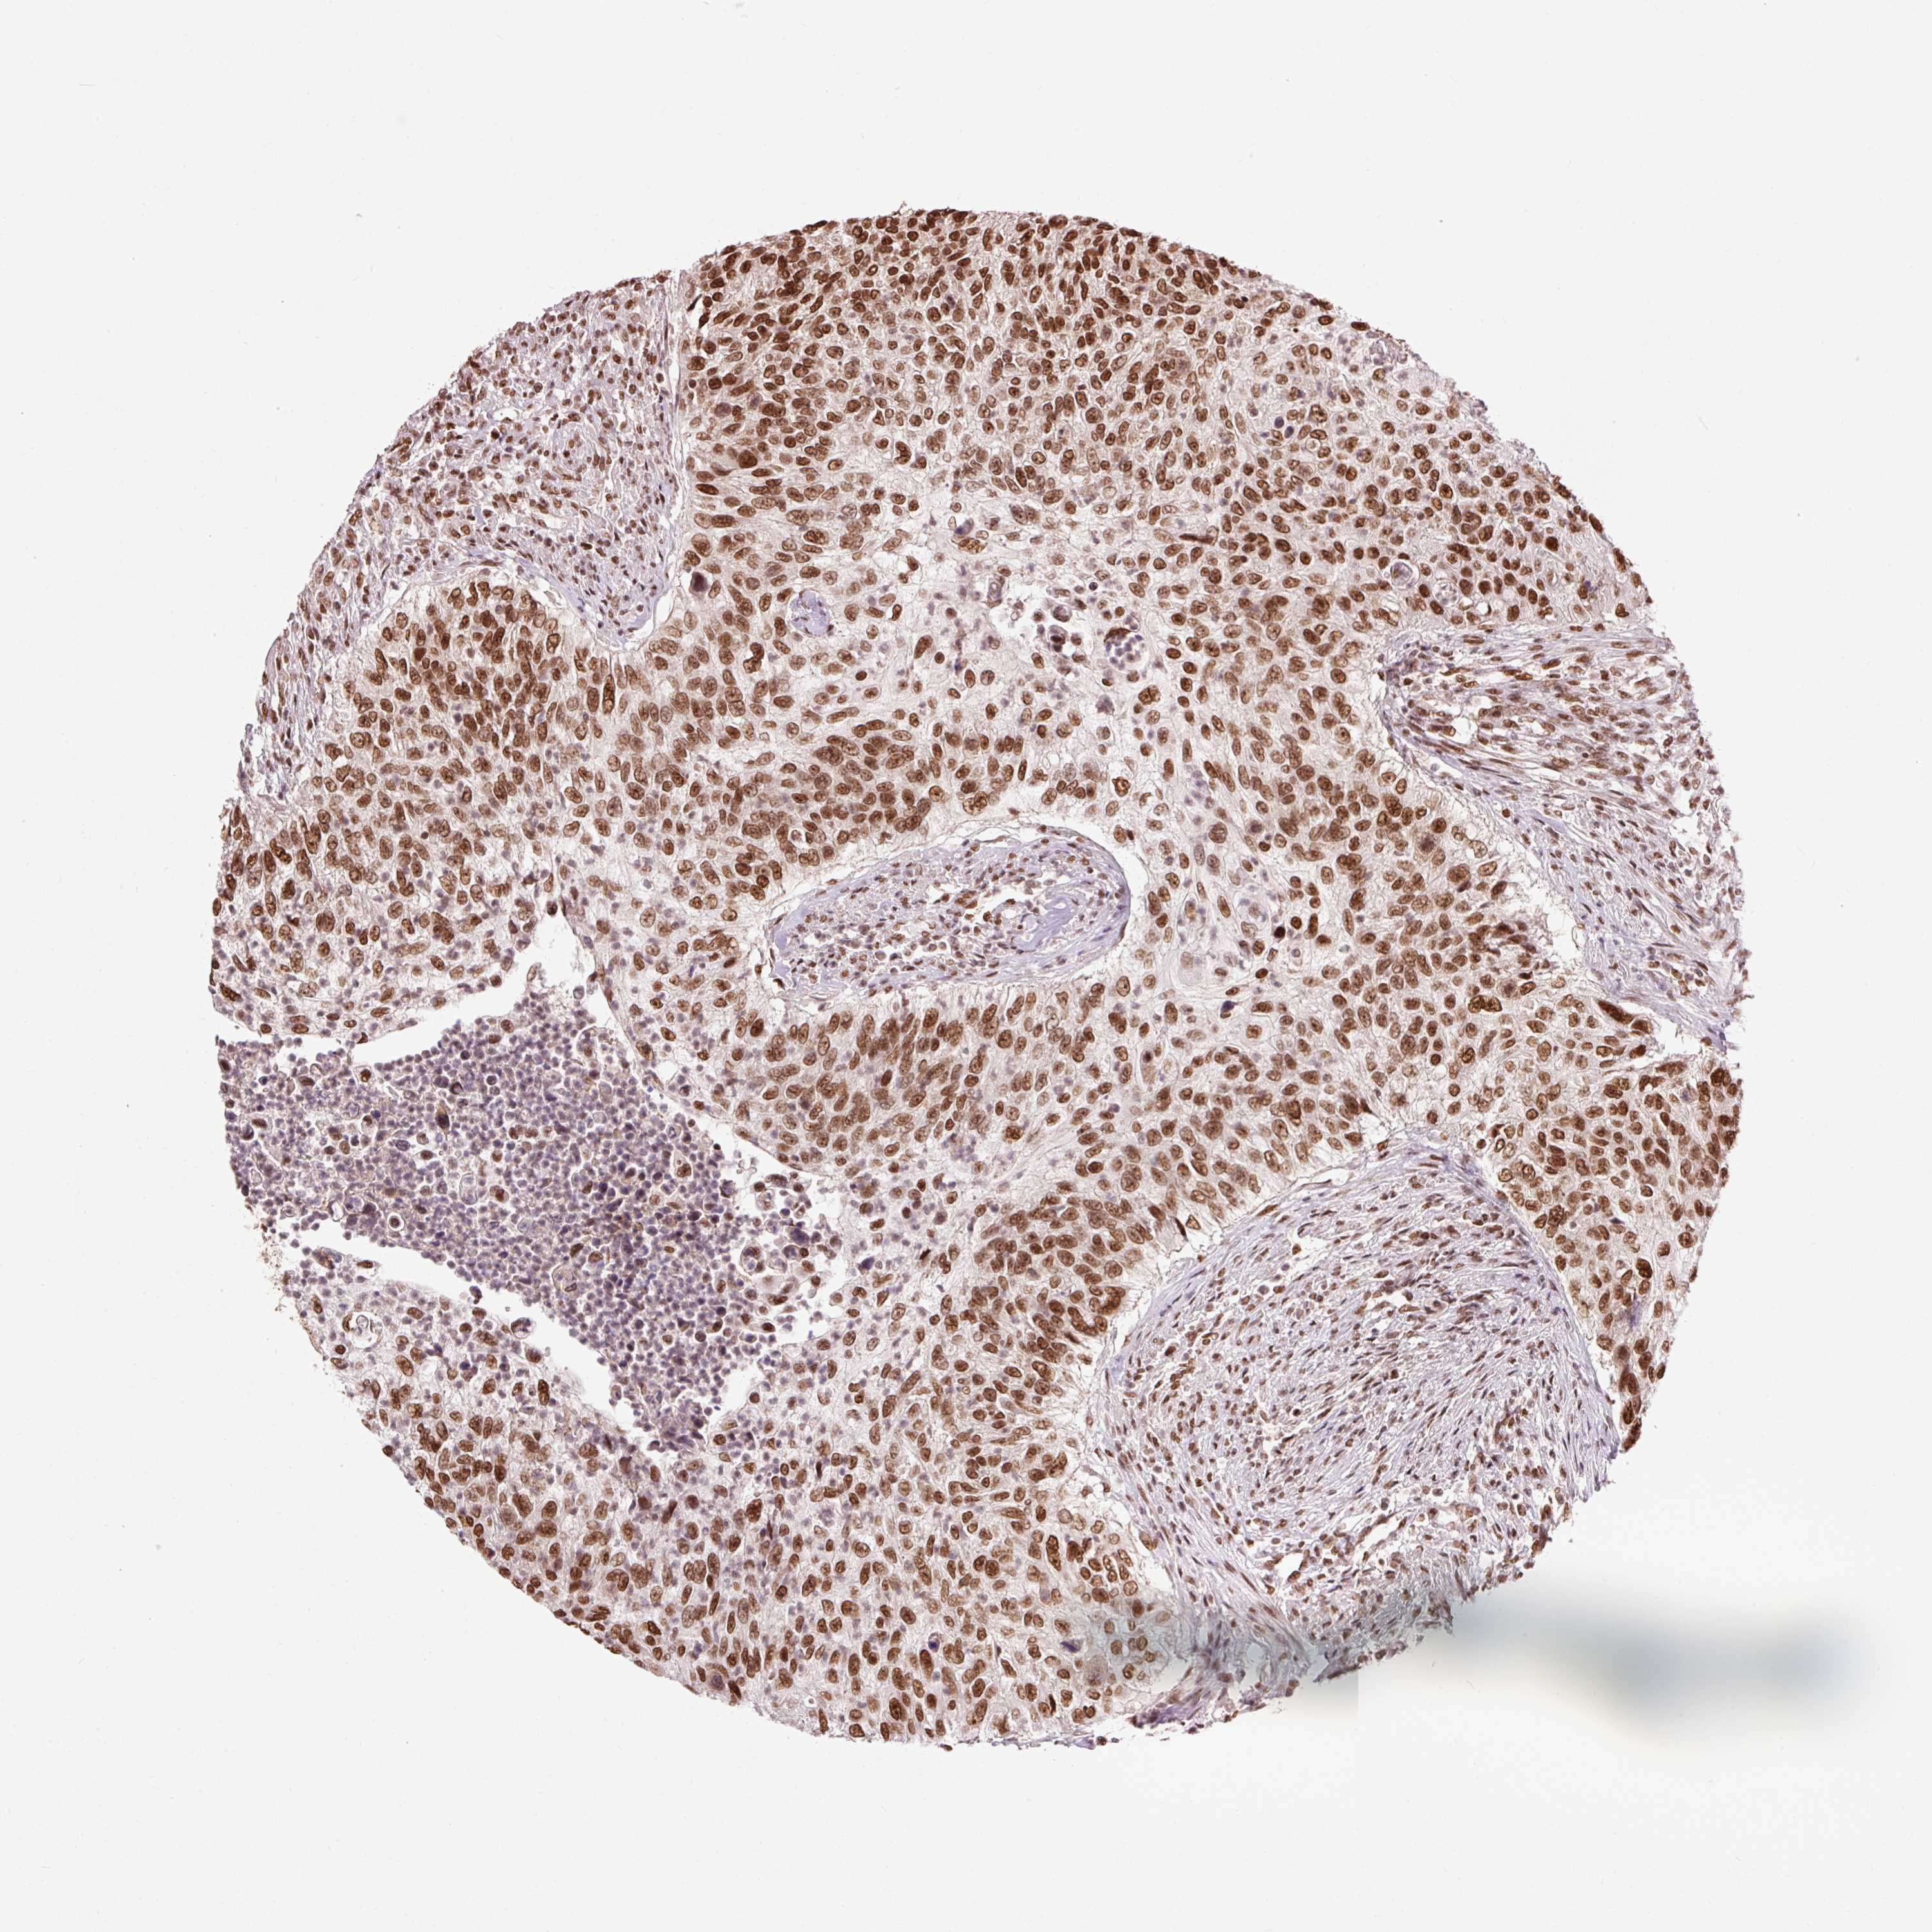

UROTHELIAL CANCER - Protein expressioni

A mouse-over function shows sample information and annotation data. Click on an image to view it in a full screen mode. Samples can be filtered based on level of antibody staining by selecting one or several of the following categories: high, medium, low and not detected. The assay and annotation is described here.

Note that samples used for immunohistochemistry by the Human Protein Atlas do not correspond to samples in the TCGA dataset.

Antibody stainingi

Antibody staining in the annotated cell types in the current human tissue is reported as not detected, low, medium, or high, based on conventional immunohistochemistry profiling in selected tissues. This score is based on the combination of the staining intensity and fraction of stained cells.

Each image is clickable and will lead to virtual microscopy that enables deeper exploration of all samples and also displays staining intensity scores, fraction scores and subcellular localization as well as patient and tissue information for each sample.

Antibody HPA052589

Staining

High

Medium

Low

Not detected

Intensity

Strong

Moderate

Weak

Negative

Quantity

>75%

75%-25%

<25%

None

Location

Nuclear

Cytoplasmic/membranous

Cytoplasmic/membranous,nuclear

Urothelial carcinoma, High grade

Urothelial carcinoma, NOS

Urothelial carcinoma, Low grade